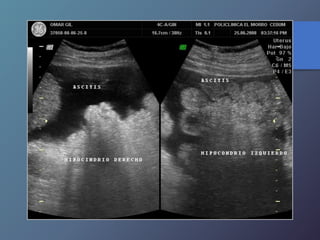

Síndrome de Budd-chiari

• Se caracteriza por la oclusión de las venas hepáticas.

• Esta relacionado con anomalías en la coagulación (policitemia

vera, leucemia crónica, traumatismos, carcinoma renal, chc

primario, embarazo).

• Clínica: Ascitis, dolor en hipocondrio derecho, hepatomegalia y

esplenomegalia.

• Ecográficamente: presencia de liquido (ascitis), aumento en los

diámetros hepáticos y esplénicos, infarto hemorrágico

hepático, aumento de la ecogenicidad en las aéreas infartadas.

• Al Doppler se aprecia aumento del flujo a nivel del lóbulo

caudado e hipertrofia del mismo, incapacidad para visualizar

las venas hepáticas.